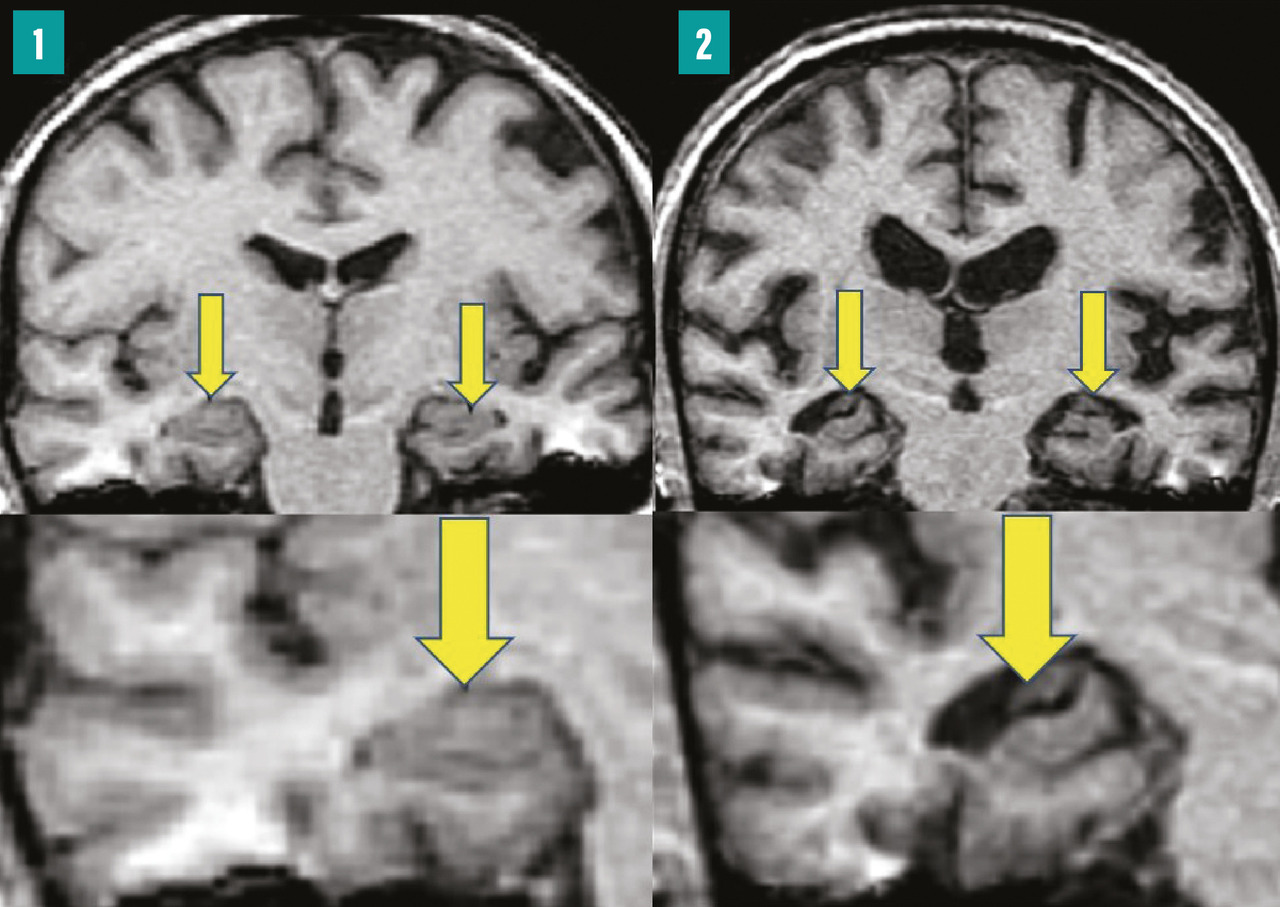

L’extension des DNF dans les hippocampes induit une perte synaptique, puis une mort neuronale, qui finit par engendrer une atrophie hippocampique, visible en imagerie par résonance magnétique (IRM) cérébrale (fig. 1 ). Celle-ci est cependant un signe survenant avec retard par rapport à la clinique. Le défi est de poser un diagnostic de plus en plus précoce de la MA, au stade des prodromes, afin de proposer une prise en charge adaptée.

L’extension des DNF dans les hippocampes induit une perte synaptique, puis une mort neuronale, qui finit par engendrer une atrophie hippocampique, visible en imagerie par résonance magnétique (IRM) cérébrale (